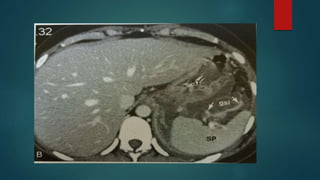

• 38.

Lesser sac  Liesbehind the stomach  Ant to pancreas  Left margin-gastro splenic ligament  Right margin–medial surface of coronary ligament  Post boundary –gastrocolic reflection&mesocolon

• 39.

Hepatorenal space –morrisonspouch  Just beneath the bare area the right peritoneal space courses between the posterior surface of segment 6 and the anterior renal fascia .  This is a relatively small potential space.  It is the most dependent portion of the right supramesocolic spaces

Right sided supramesocolic spaces The right sub diaphragmatic space is limited anteriorly by the falciform ligament and posteriorly by the upper layer coronary ligament